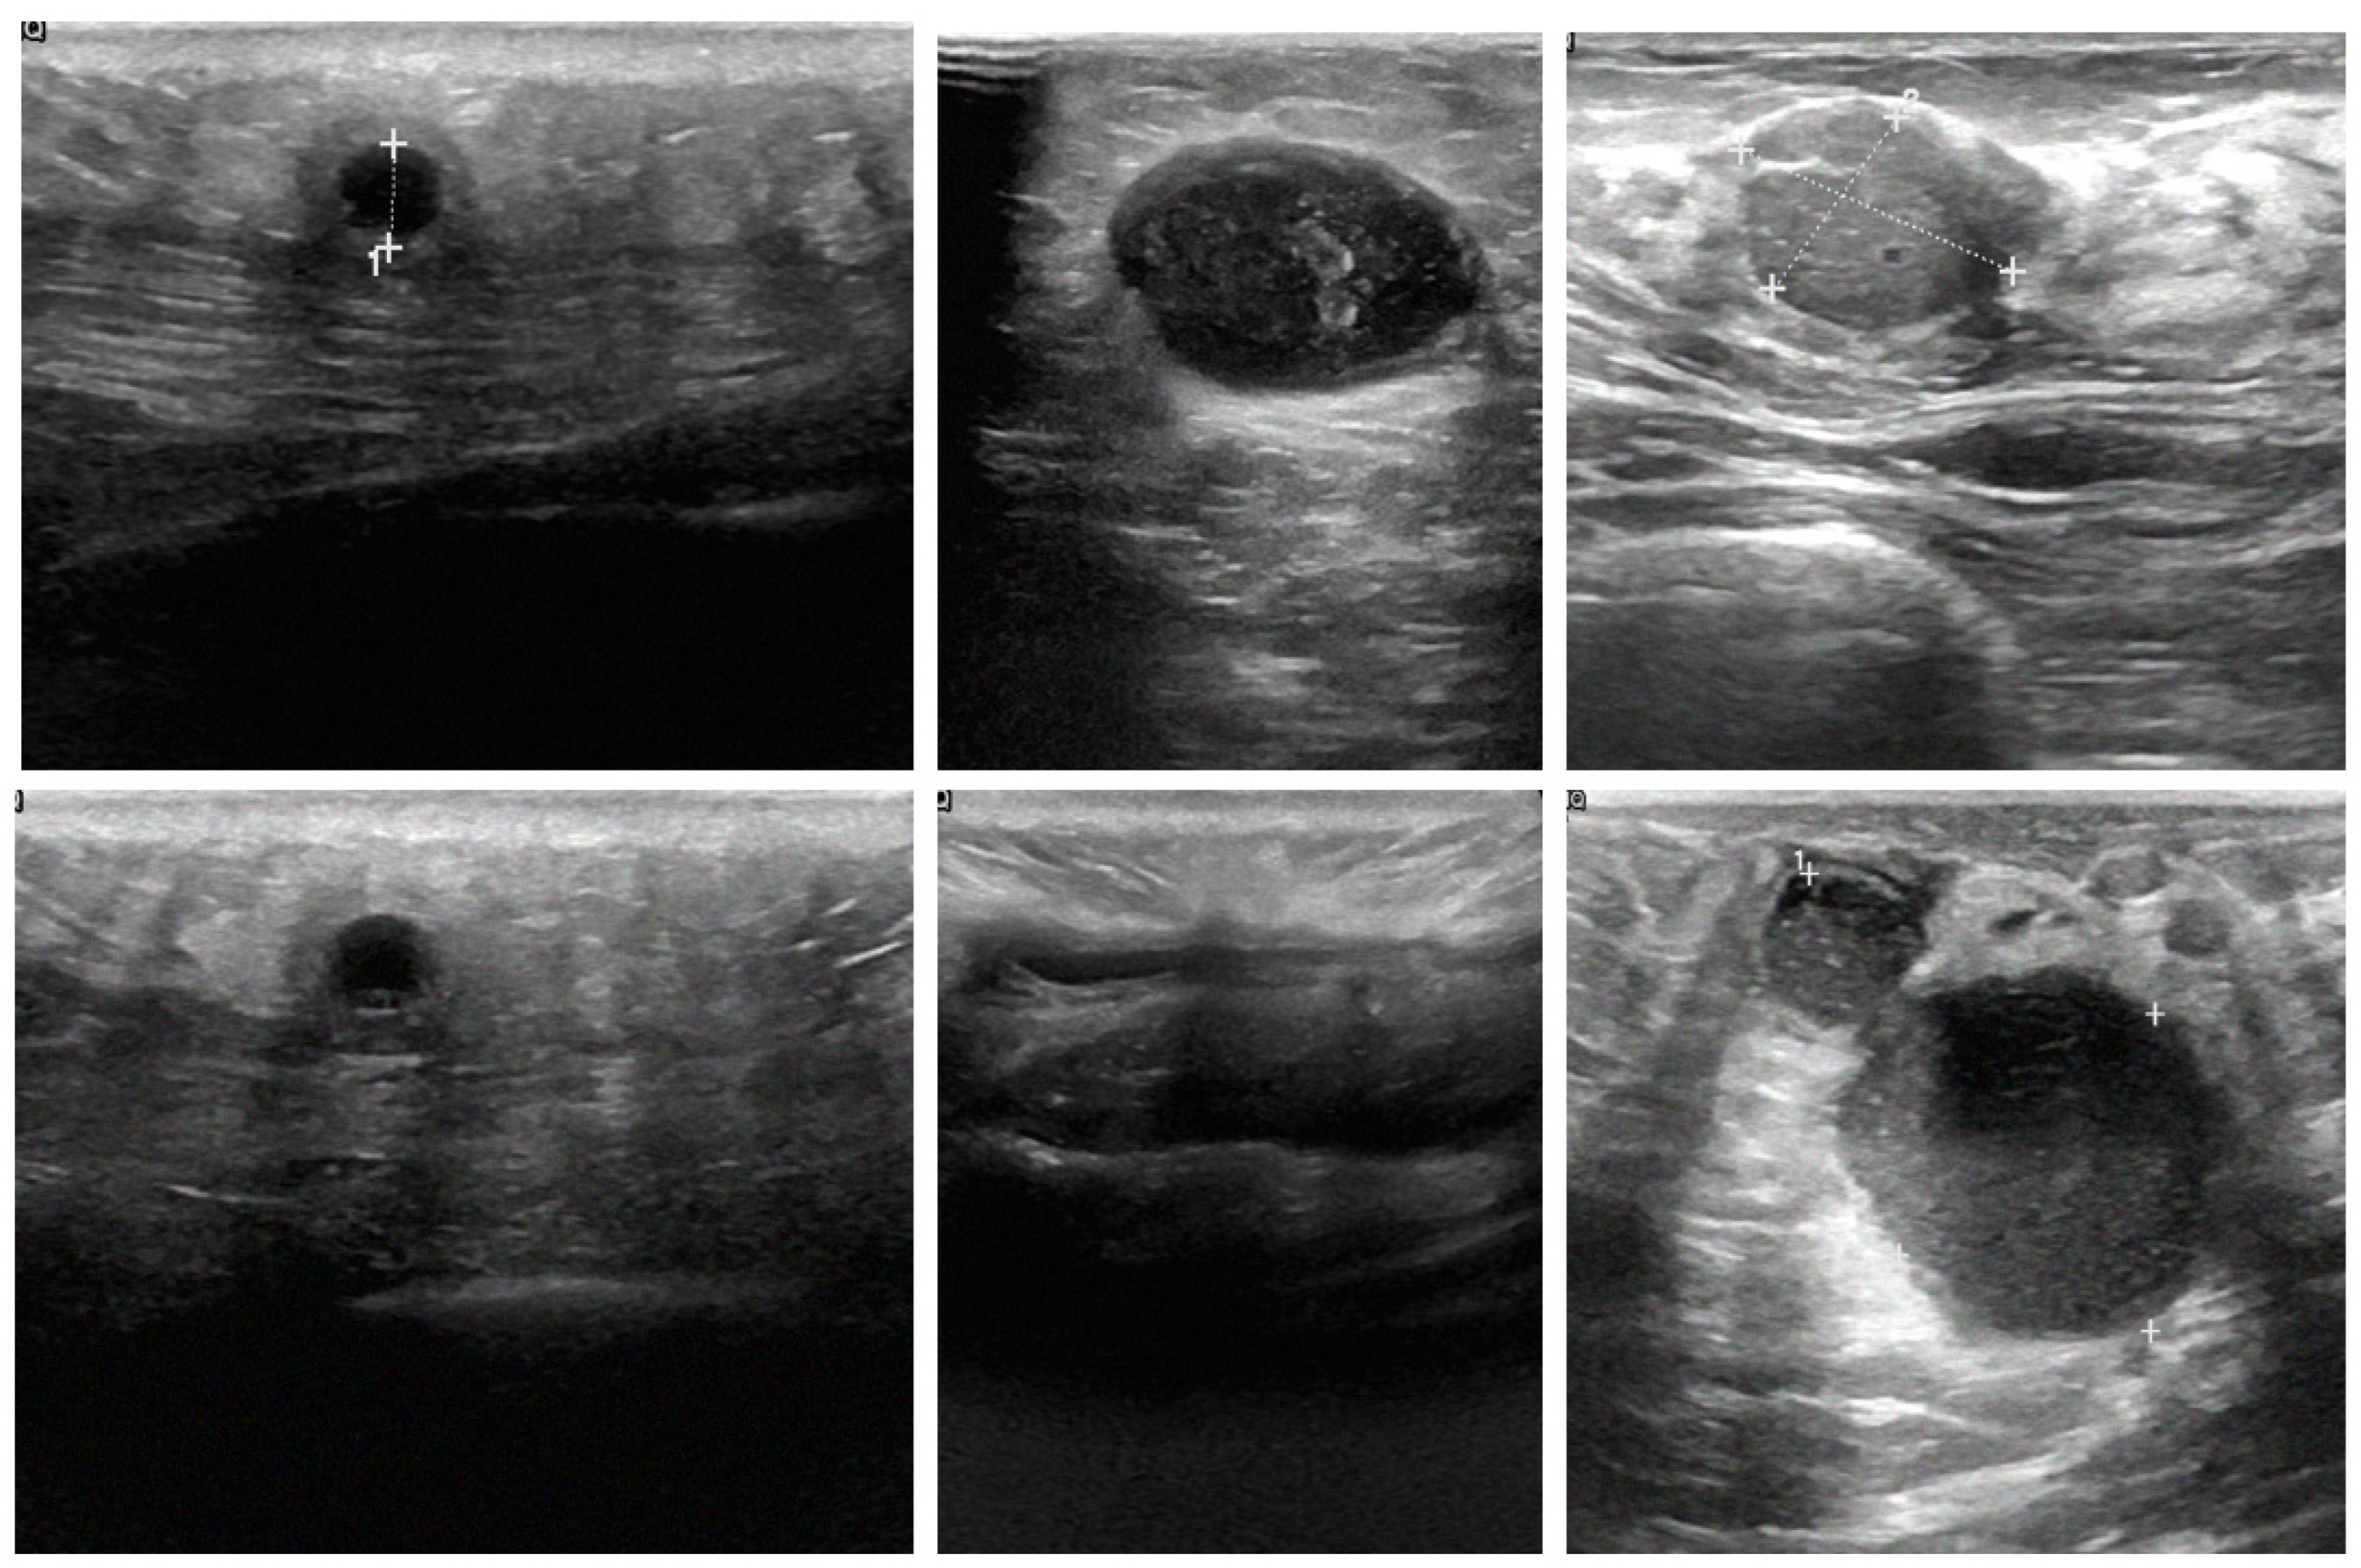

A key contribution of this study is the successful integration of cross-modality imaging, which combines mammography and ultrasound images, to enhance classification accuracy. By fusing features from these different imaging modalities, the models were able to leverage the complementary strengths of each, resulting in more robust and accurate classifications. For example, mammography excels at visualizing dense structures, while ultrasound provides detailed images of soft tissues. This integration allowed the AI models to perform more comprehensive analysis of breast tissue, which is crucial for accurate tumor detection. Ultrasound images, as shown in Figure 9A–C, depict various breast tissue characteristics, while mammography images, as shown in Figure 9D–F, illustrate different breast tissue densities. These images were instrumental in training and testing the AI models for breast cancer detection and classification.

Figure 9.

Comparison of breast tissue textures in sonography and mammography images.